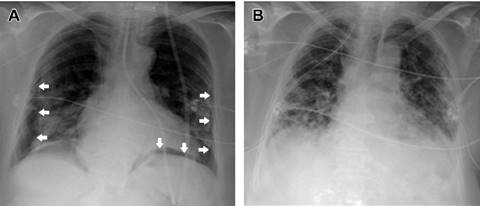

Tras el procedimiento se solicitó un control radiológico para la comprobación de la posición de la sonda, mientras la paciente se mantuvo clínicamente estable. Sin embargo, en la radiografía se objetivó el paso de la SNG a través del bronquio principal derecho, alcanzando el lóbulo inferior y volviendo al bronquio, con un pequeño neumotórax derecho concomitante. Se retiró la sonda y de acuerdo con cirugía torácica se decidió un manejo inicial conservador, dado el escaso tamaño y repercusión del neumotórax. Se colocó otra sonda, con la misma técnica, con buena tolerancia y nuevamente sin tos ni otras complicaciones durante la colocación. No obstante, a los pocos minutos, la paciente comenzó con disnea, taquipnea y desaturación a 88%. La radiografía mostró la SNG en el bronquio principal izquierdo y la presencia de neumotórax bilateral (Figura 1A).

Figura 1: A) Imagen de la sonda nasogástrica posicionada a través del bronquio izquierdo y neumotórax bilateral (flechas). B) Reexpansión de los neumotórax tras la retirada de la sonda y la colocación de dos drenajes torácicos.

Se retiró la SNG, se colocaron drenajes torácicos bilaterales, con lo que se logró la expansión de ambos pulmones (Figura 1B), y se inició soporte con oxigenoterapia de alto flujo, mejorando la sintomatología respiratoria y la hipoxemia. A la mañana siguiente se colocó una nueva SNG con control endoscópico. Los drenajes torácicos fueron retirados cuatro días después sin complicaciones y la paciente fue dada de alta a la planta de hospitalización 48 horas después de retirados los drenajes.